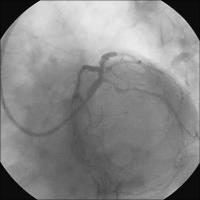

Linke Koronararterie RAO/Kranialprojektion

Abbildung 1: 50 % Ostiumstenose Hauptstamm, Bifurkationsstenose LAD – 1. diagonaler Ast (echte Bifurkationsstenose Typ IV ICPS- Klassifikation ), Y-konfigurierter Abgang des Seitenastes. Kollateralen zur verschlossenen RKA.

Keywords: BifurkationsstenoseKardiologieKoronarangiographieOstiumstenose